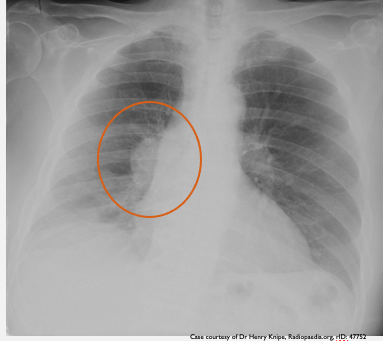

What does this CXR indicate? - Pneumoperitoneum - Pneumothorax - Pulmonary oedema - Consolidation - Pleural effusion

What does this CXR indicate? - Pneumoperitoneum - **Pneumothorax** - Pulmonary oedema - Consolidation - Pleural effusion